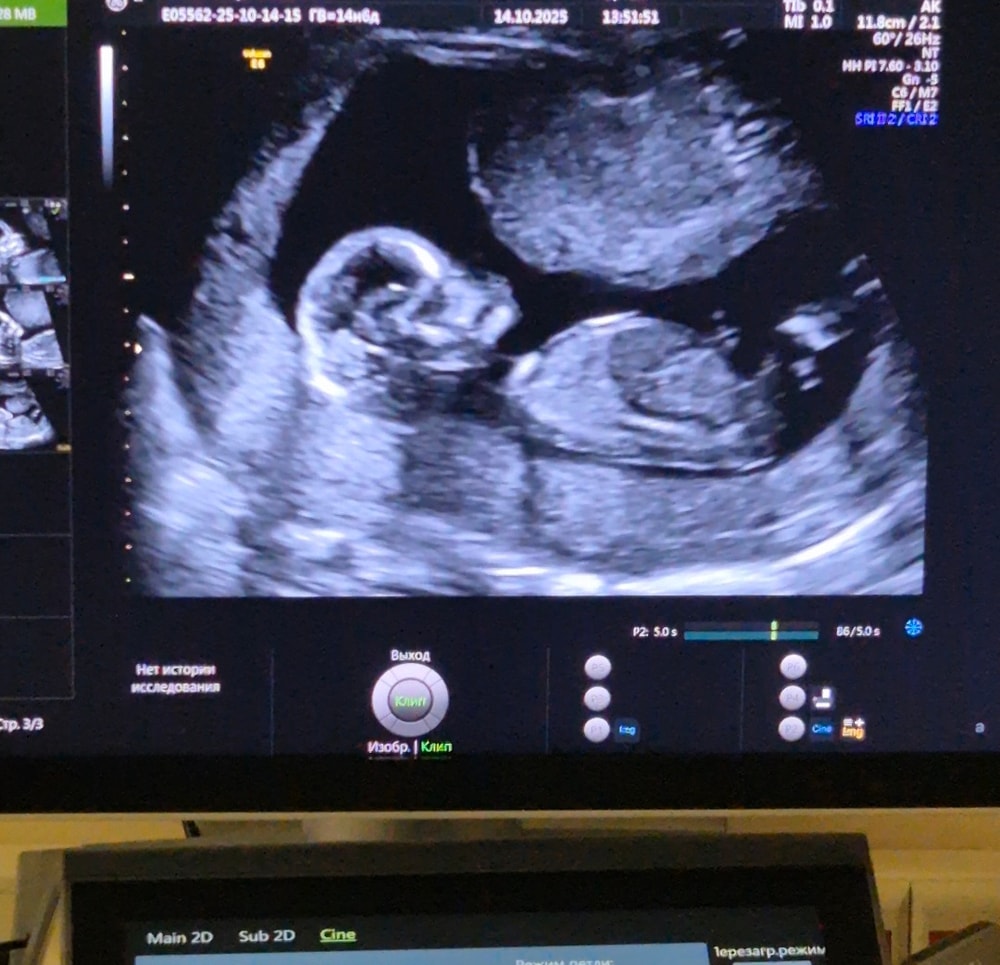

Девочка - 15 недель тут по-моему … Изображение

29.10.2025